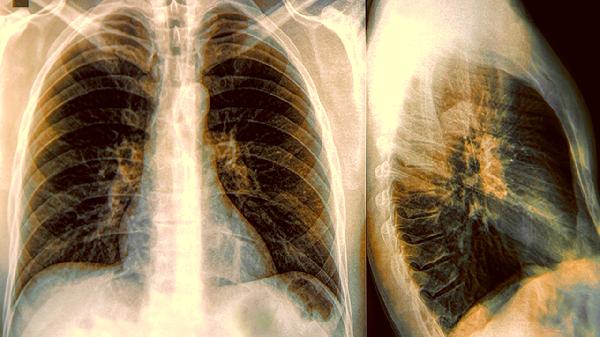

浙贝母、苦杏仁等药物成分能化痰散结,对肺结节、淋巴结核等良性增生病变有辅助治疗作用。对于尘肺病等职业性肺病患者出现的肺纤维化病灶可能有一定改善效果。

使用清肺散结丸期间应忌食辛辣刺激性食物,避免吸烟及接触粉尘。肺结节患者需定期复查胸部CT观察病灶变化,肿瘤患者不能替代放化疗等主要治疗手段。出现药物过敏反应或症状加重时应立即停药就医,孕妇及哺乳期妇女慎用。